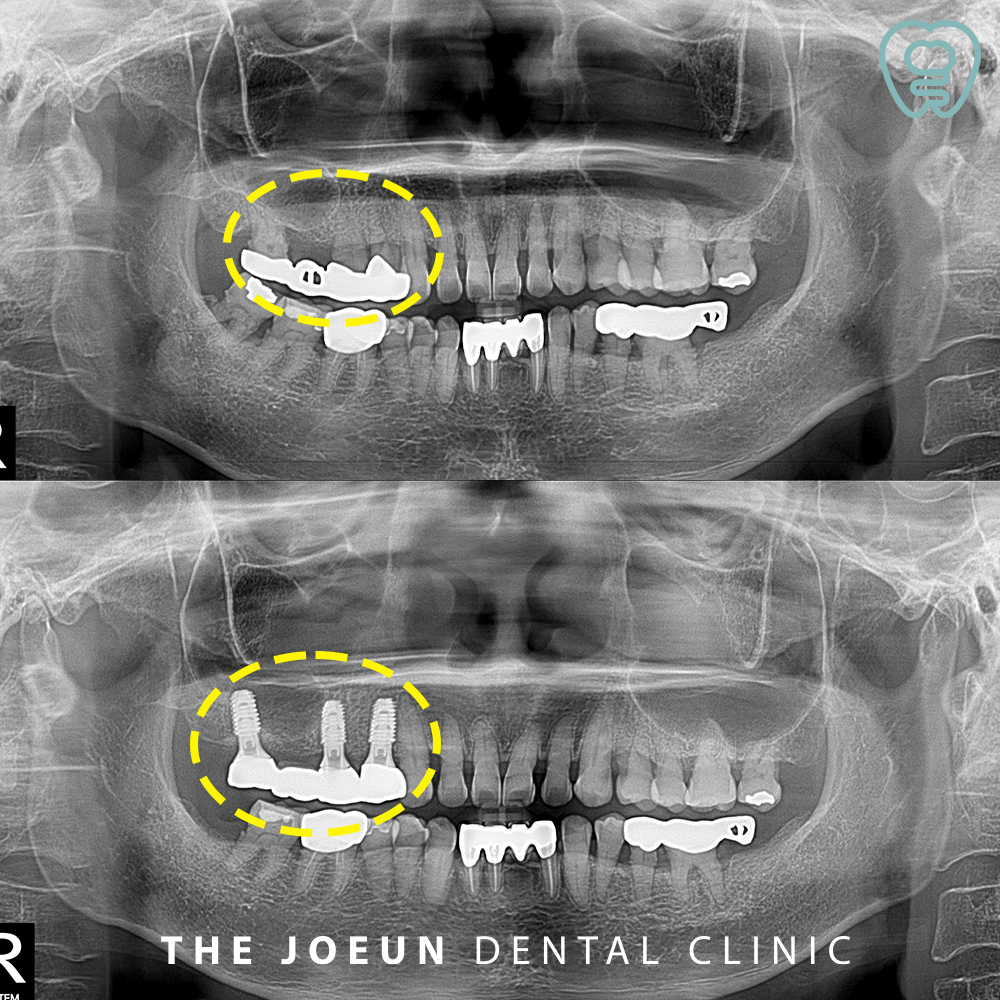

오늘은 예후가 좋지 않은 브릿지를 발치한 후 상악동 거상술을 동반하여 강창역어금니임플란트를 즉시 식립하신 환.자분을 소개해 드리려고 합니다.

환.자분께서는 오른쪽 위 오래전 씌워 놓은 어금니 부위가 흔들리고 불편하시다며 내원해 주셨는데요. 오래전 브릿지 치료를 받으신 부위였지만 관리가 제대로 되지 않아 염증으로 인해 잇몸뼈가 많이 녹아 흔들리는 상태였고, 치아를 상실하신 부위가 오래되었다 보니 상악동이 아래로 많이 내려와 있음을 확인할 수 있었습니다. 따라서 오래된 브릿지를 제거하고 상악동 거상술을 동반한 임플란트 식립 계획을 수립하였습니다.

오른쪽 위 브릿지와 아래쪽 사랑니까지 발치한 모습인데요.

당일 쳐져 내려와 있는 상악동을 들어 올리는 상악동 거상술을 동반한 임플란트 식립을 진행하였습니다.

2024년 2월 26일에 시작하여 6월 20일인 약 4개월여만에 최종 보철물까지 마무리를 하였는데요.